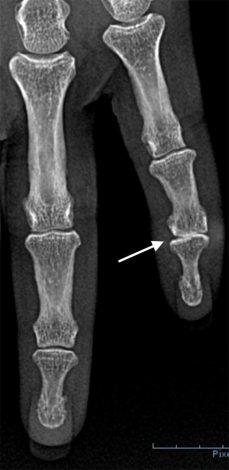

Raio-X demonstrando artrose da articulação interfalângica distal.

Um Rx é suficiente para avaliar se há uma artrose na articulação. Na maior parte dos casos, é visível um pequeno crescimento ósseo por baixo do quisto ("bico de papagaio"/osteófito).